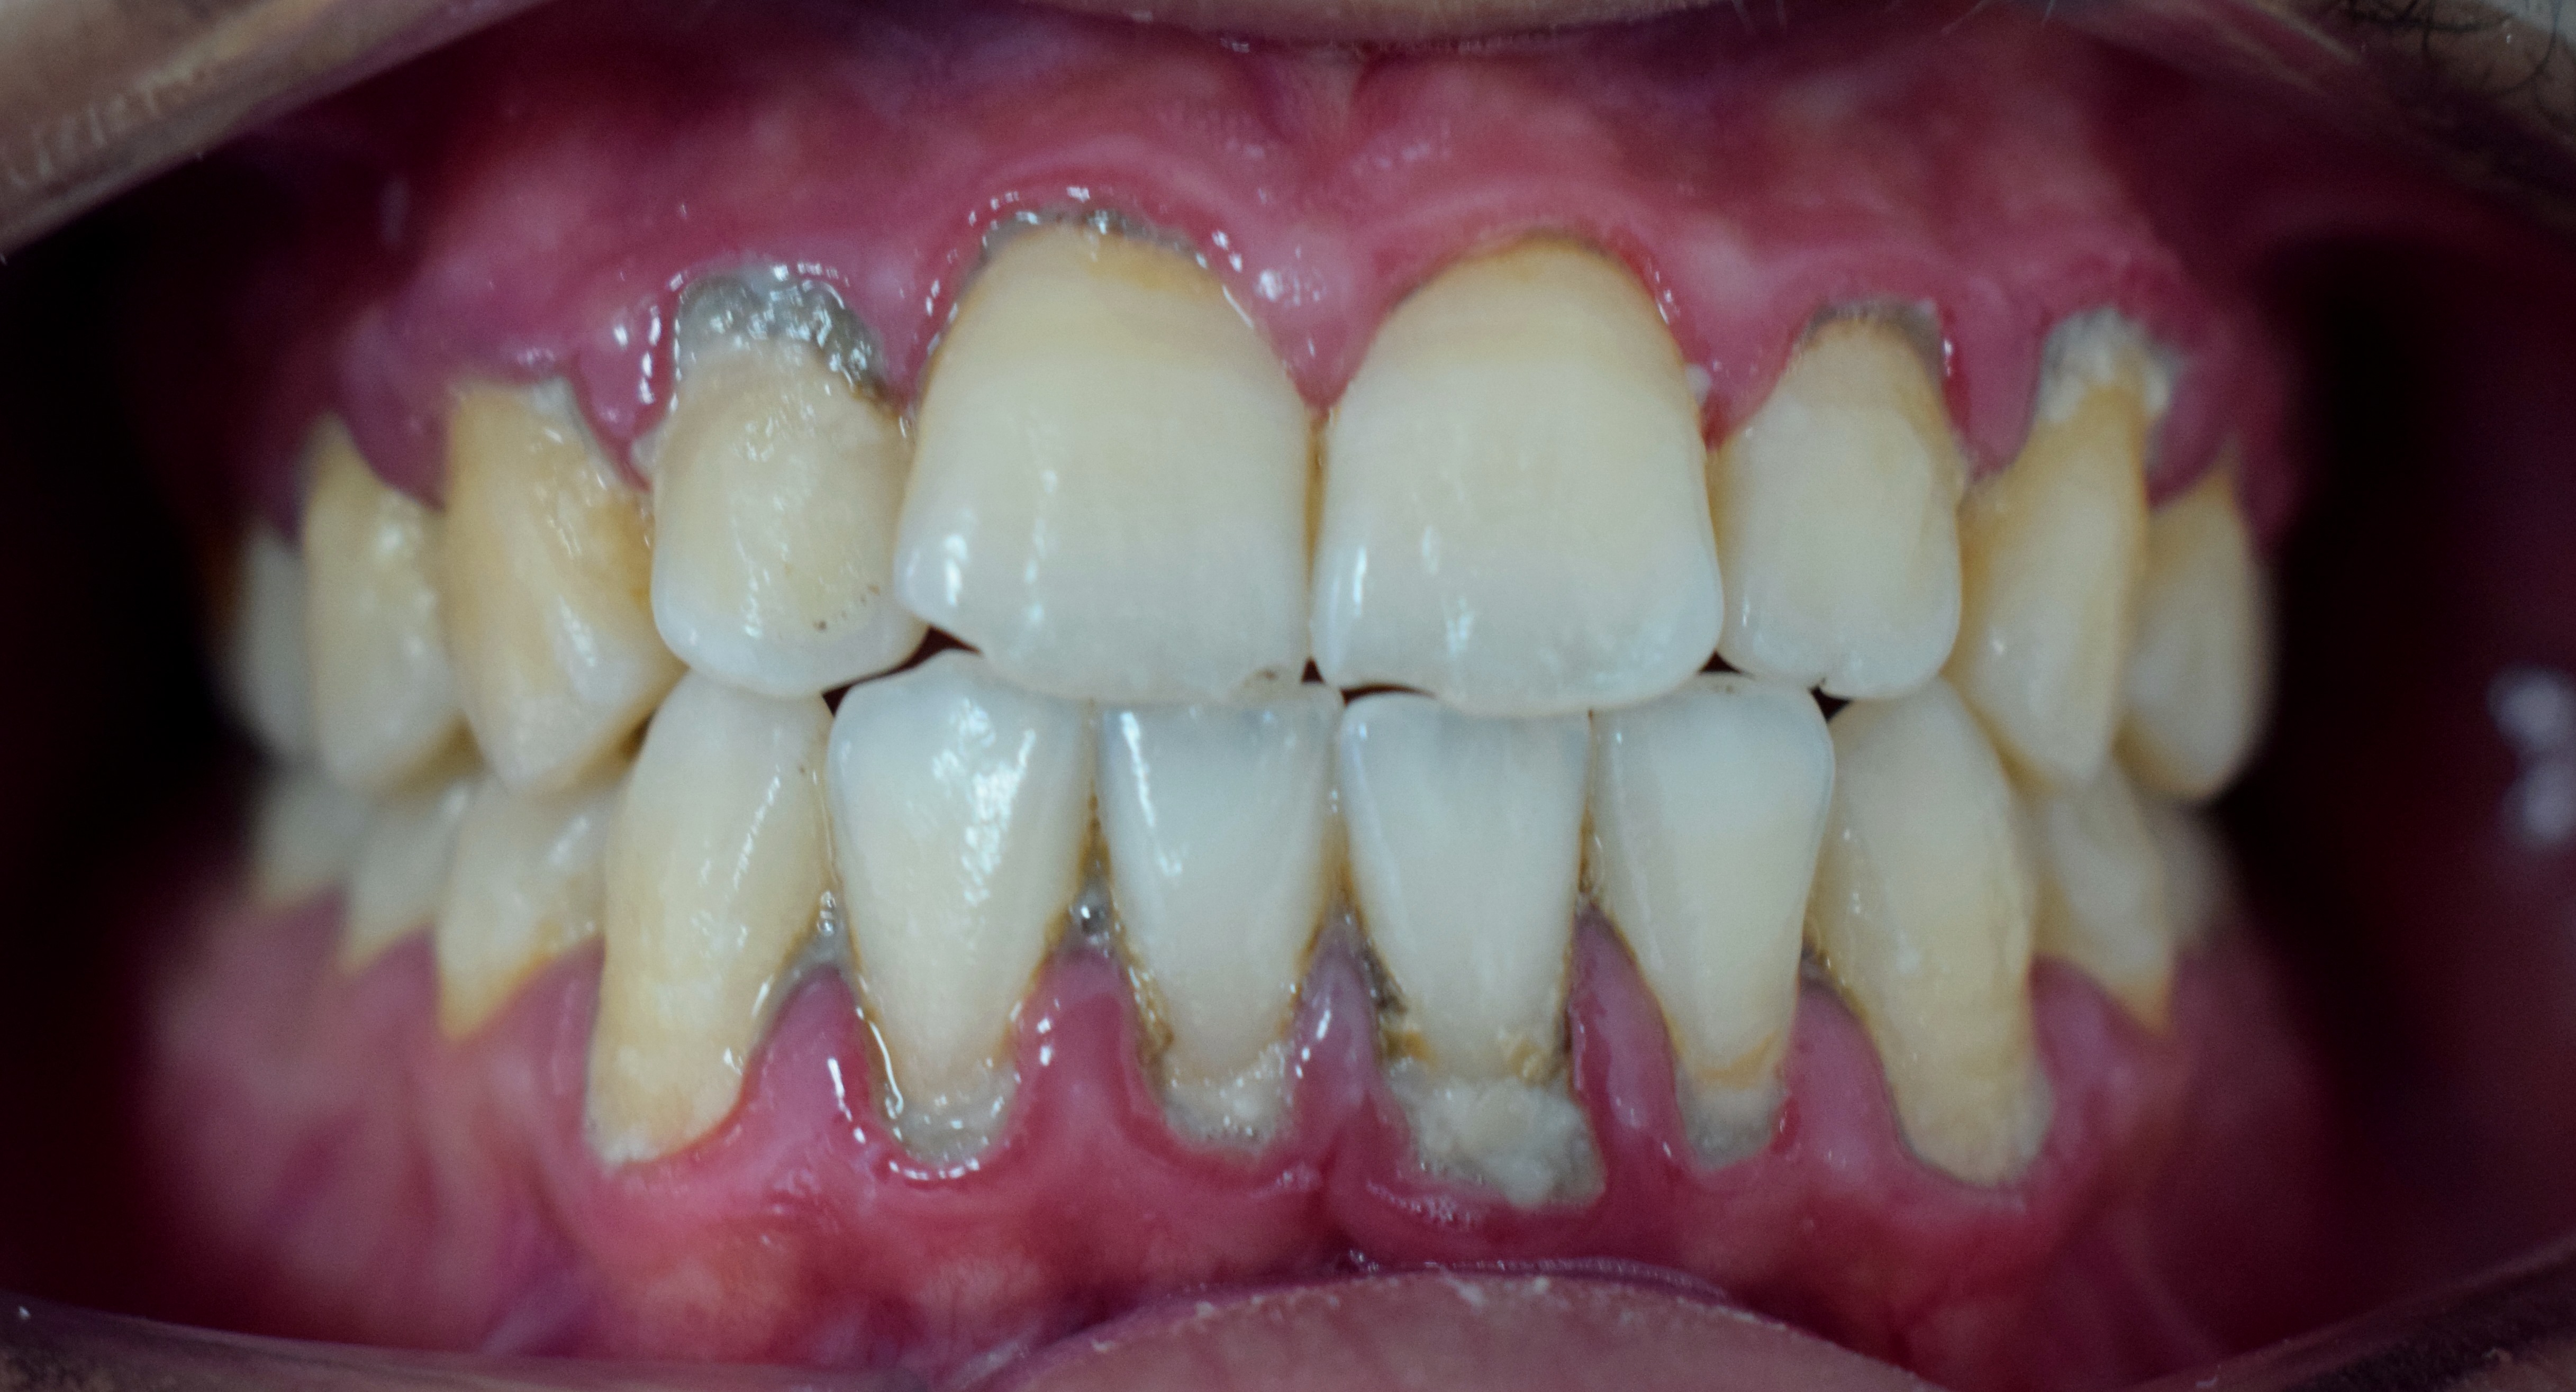

치아 표면에 부착된 치석

치석은 오랫동안 제거되지 않고 남아있는 치태가 타액이나 잇몸 고랑(치은구) 삼출액에서 나오는 칼슘에 의해 단단하게 굳어져 형성된다.[47] 치주 조직의 상태는 치주 조직이 파괴되는 정도와 치석이 쌓이는 양에 크게 관계한다.[47] 치석 자체는 직접적인 병원성이 없지만, 표면이 거칠어 치태가 쉽게 붙고 쌓이게 만드는 원인이 된다.[47] 축적된 치태는 치주 조직에 염증과 파괴를 일으키는 주요 원인이 된다.[47] 잇몸(치은)의 변연을 기준으로 치은 연상에 형성되는 것을 치은 연상 치석, 치은 연하에 형성되는 것을 치은 연하 치석이라고 하며, 그 성질은 크게 다르다.[47]

3. 1. 치은 연상 치석

3. 2. 치은 연하 치석

치은 연하 치석은 잇몸 아래, 치은구(잇몸 고랑) 또는 치주낭(잇몸 주머니) 내에 형성되는 흑갈색의 치석이다.[47] 치은구 삼출액,[48][49] 감염된 치주 조직의 삼출액,[49] 혈액[48] 등에서 유래한다.[47] 치은 연상 치석에 비해 형성 속도는 느리지만, 밀도가 높고 부착력이 강해 제거하기 어렵다.[47][49]